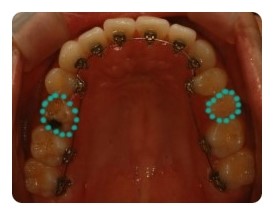

( 상악비교 )

▲ 발치 전 - 왼쪽유치 1차삭제, 오른쪽영구치 발치 예정

▲ 6월 - 스크류식립 후 본격적으로 상악당기기 1개월차

▲ 8월 - 3개월차

▲ 10월 - 5개월차

조신하지못한 저의 잦은 어금니 브라켓탈락 ㅠㅠ 에도 불구하고 잘 이동하고 잇는듯해요